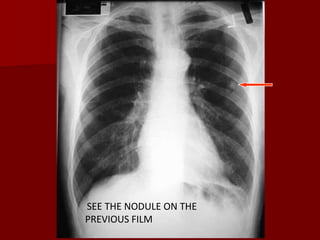

Penetration

SEE THE NODULE ON THE

PREVIOUS FILM